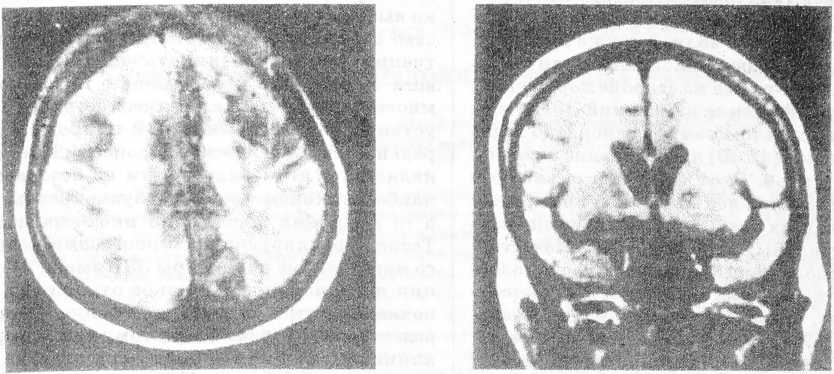

Рис. 1. Магнитно-резонансная томограмма (Т2-взвешенное изображение) больной 67 лет с очаговой ишемией мозга на фоне дисциркуляторной энцефалопатии. Резко выраженный лейкоарайоз в перивентрикулярной области

Большую диагностическую проблему представляет выявление при КТ и МРТ постишемических изменений мозга в виде лейкоарайоза (рис. 1) и так называемых “молчаливых” инфарктов, протекающих клинически скрыто (рис. 2). Нами не выявлено линейной зависимости между степенью лейкоарайоза (слабая, умеренная, выраженная) и клинической тяжестью церебрального сосудистого процесса.

Поэтому мы не разделяем мнения тех авторов, которые считают лейкоарайоз морфологическим маркером сосудистой деменции [10], хотя и не отрицаем его роли как предиктора (показателя возможности) появления у таких больных когнитивных нарушений. Гораздо большая роль в возникновении когнитивных расстройств и внезапном углублении очаговых неврологических симптомов принадлежит, по нашим данным, декомпенсации старого очага, то есть “немого” инфаркта (рис. 2).

Рис. 2. Магнитно-резонансная томограмма (Т2-взвешенное изображение) той же больной. Отчетливо видна постинфарктная киста в правой затылочной доле (“немой” инфаркт)